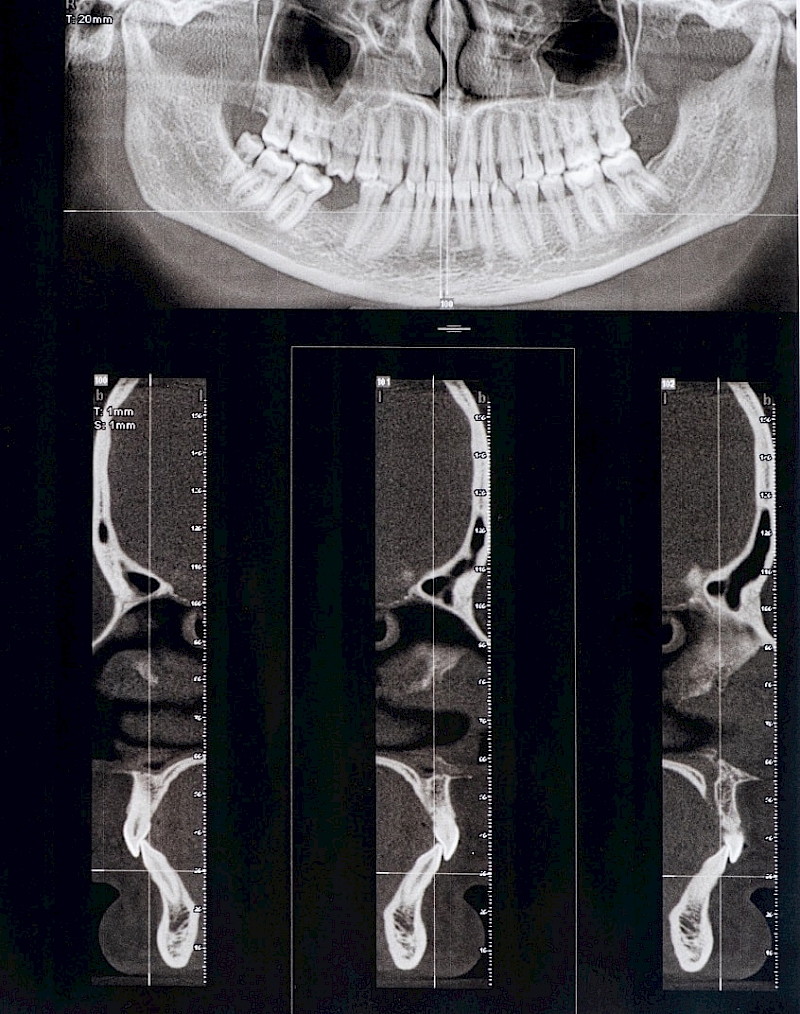

Methods by which you can check your jaw joint

Put your fingers in your ears, open and close your mouth several times. Do you feel clicking sounds?

Stand in front of the mirror and slowly open and close your mouth. Is there a shift to the other side or pain when opening?

Slide your jaw from one side to the other and note if there is pain.

Check the Sensitivity of Your Muscles

Place your fingers on the area where your joints are, which are slightly in front of your ears, apply pressure to your cheek area.

If you feel any discomfort or pain in your jaw joint, consult a dentist who specializes in TMJ.